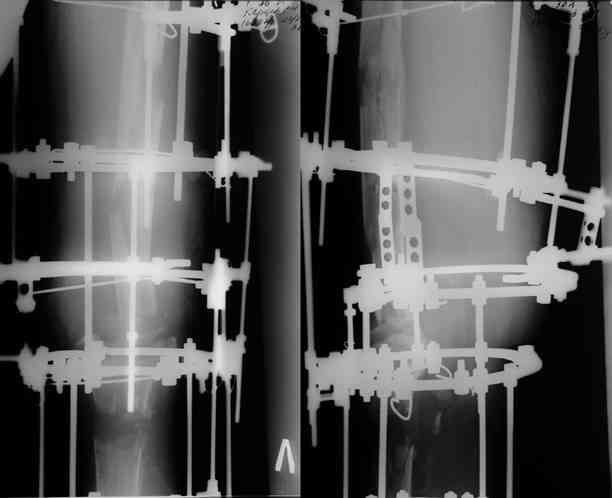

После нескольких некрэктомий, проведения аутодермопластики и заживдения ожоговой раны через 2 месяца после травмы произведен открытый остеосинтез левой бедренной кости штифтом и пластиной (деротационной) [image 01, 02]. Через 1 год и 7 месяцев после травмы у больного диагностированы ложный сустав и хронический остеомиелит левой бедренной кости. Произведено удаление металлических фиксаторов, секвестрэктомия и остеосинтез бедренной костивнешним двухплоскостным стержневым аппаратом [image 03, 04] .